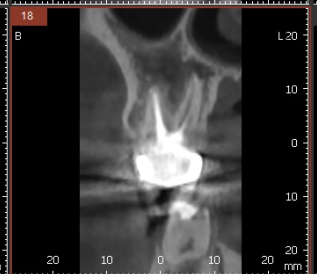

3D ct 등을 통해 정밀한 검사를 진행한 결과,

치아 뿌리 주변의 염증으로 한쪽 뼈를 녹였네요.

ct 상 한쪽 뼈만 녹아있는 상황이라

반대편 뼈에 기대해보면서

x-ray를 봐서는

염증이 없어진건지 잘 모르시겠죠~?

변화가 된 모습만 비교해드릴께요~

뿌리 절반 이상 염증들이

3달의 치료과정을 통해

손톱만큼 줄어들었습니다.

이제 뿌리 끝 까만 부분

거의 보이지 않습니다.

염증이 남아있으면 제대로 뼈가 차지 않는대요.

깨끗하게 염증이 없어졌기 때문에

까맣게 녹아 버린 뼈가

다시 하얗게 채워진 모습을 볼 수있네요~